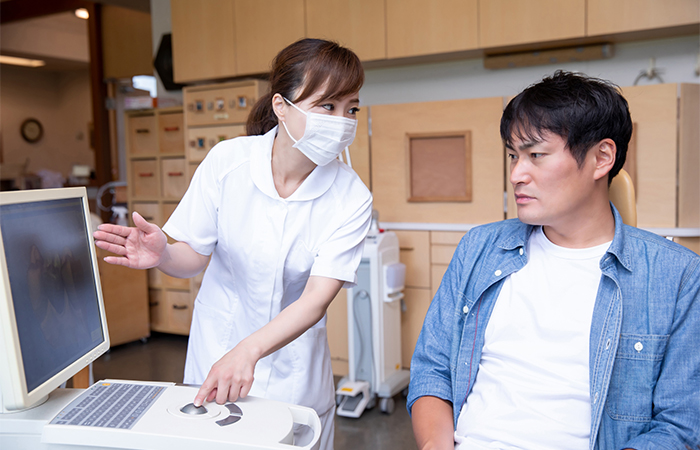

また、患者様の立場に立ってしっかりしたカウンセリングを行い、思いやりをもって治療にあたりますので、どのようなことでもお話しください。

しっかりとしたカウンセリングで

治療をサポート

根管治療では、根管内に細菌を残さないよう徹底的に清掃を行うため通院回数が多くなります。

当院では、丁寧なカウンセリングを行った上で治療を進めています。途中で治療を終わることがないよう患者様の治療をサポートしますので、通院についてのご要望などがありましたらお聞かせください。

また、被せ物は、保険診療のものと自由診療のものを患者様のご希望で選ぶことができます。それぞれの違いをわかりやすく説明し、患者様に合った適切な被せ物をご提案いたします。

検査とカウンセリングを

行います

根管治療では、立体的にお口の中を撮影できる「歯科用CT」を使って、事前にしっかり検査を行います。歯や顎の状態、神経や血管の位置を詳しく把握できるため、診断の精度を高めることが可能です。

また、カウンセリングでは患者様の歯の状況をわかりやすくご説明しますので、どのような被せ物を選択するかなどを決めていきましょう。